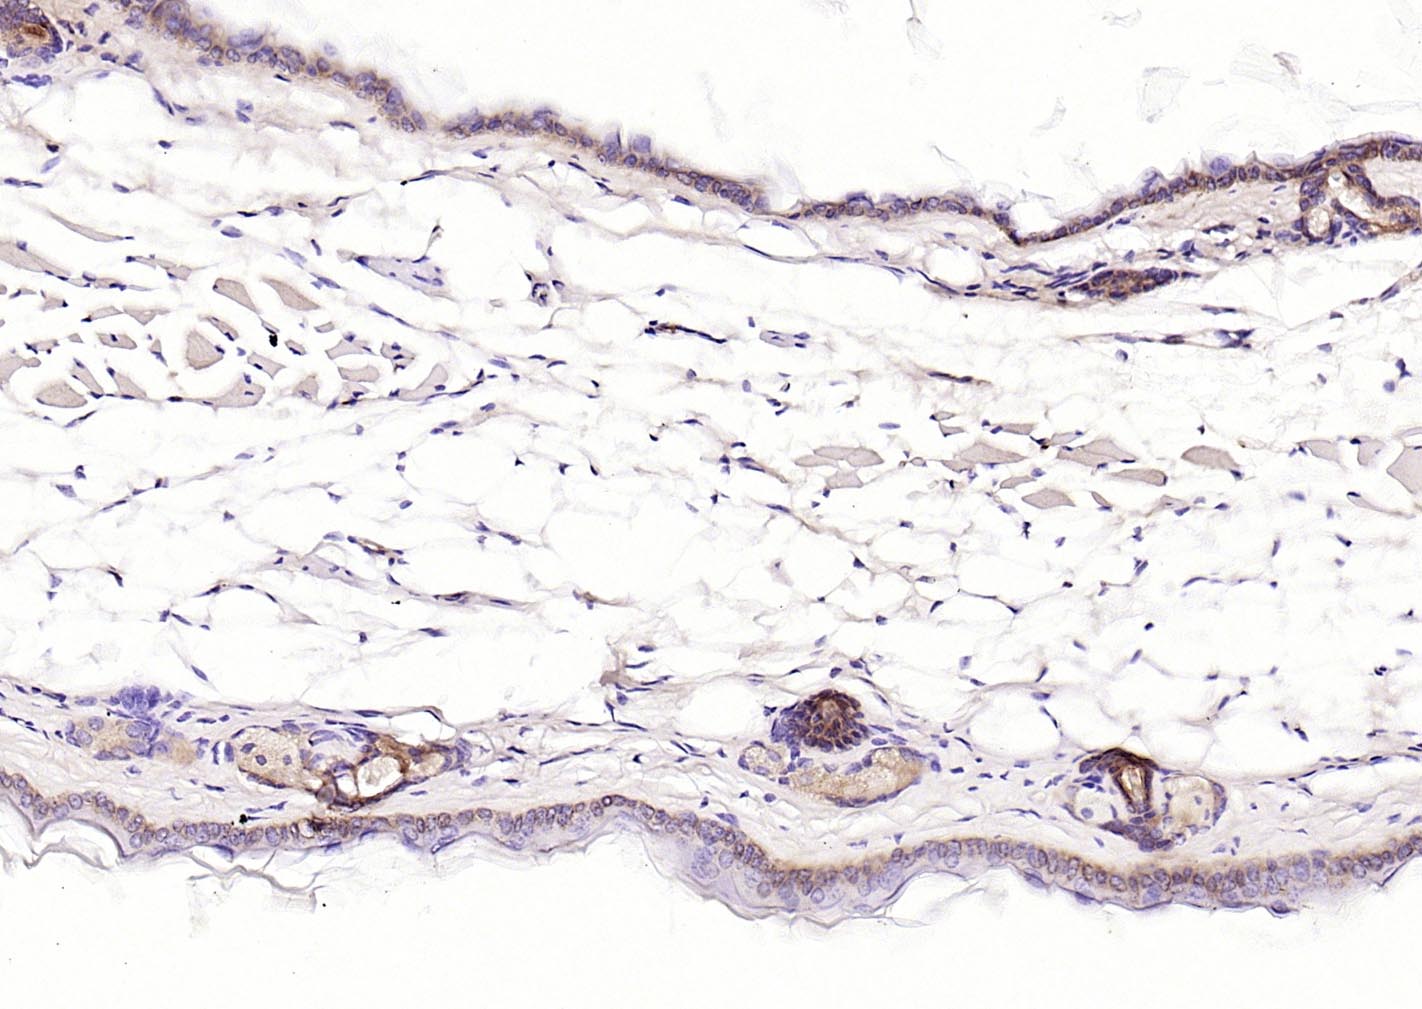

P-CK广谱细胞角蛋白(AE1/AE3)主要标记角化上皮、复层鳞状上皮、复层上皮、增生的角化上皮和单层上皮,用于鳞癌,各种腺癌 、移行上皮癌,小细胞癌,恶性间皮瘤、生殖细胞肿瘤,部分滑膜肉瘤、平滑肌肉瘤等表达。

广谱细胞角蛋白PCK单克隆抗体-bsm-34137M广谱细胞角蛋白PCK单克隆抗体-bsm-34137M广谱细胞角蛋白PCK单克隆抗体-bsm-34137M广谱细胞角蛋白PCK单克隆抗体-bsm-34137M广谱细胞角蛋白PCK单克隆抗体-bsm-34137M广谱细胞角蛋白PCK单克隆抗体-bsm-34137M广谱细胞角蛋白PCK单克隆抗体-bsm-34137M广谱细胞角蛋白PCK单克隆抗体-bsm-34137M广谱细胞角蛋白PCK单克隆抗体-bsm-34137M广谱细胞角蛋白PCK单克隆抗体-bsm-34137M广谱细胞角蛋白PCK单克隆抗体-bsm-34137M广谱细胞角蛋白PCK单克隆抗体-bsm-34137M广谱细胞角蛋白PCK单克隆抗体-bsm-34137M广谱细胞角蛋白PCK单克隆抗体-bsm-34137M广谱细胞角蛋白PCK单克隆抗体-bsm-34137M

IHC-PHuman, Mouse, Rat1:100-500